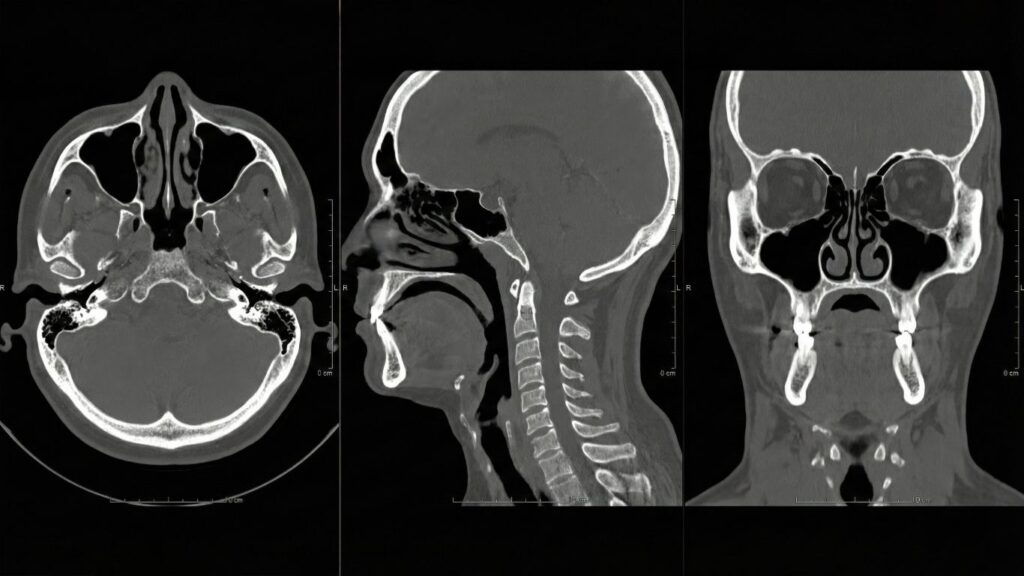

Tomografías Precisas y Rápidas en Querétaro

En Altaria, estamos comprometidos con ofrecer tomografías modernas y eficaces que facilitan diagnósticos médicos precisos y claros. Nuestras tomografías en Querétaro son reconocidas por su rapidez y calidad, permitiendo así a los profesionales de la salud tomar decisiones informadas que benefician a los pacientes. Al ser parte de un avance significativo en el ámbito de […]